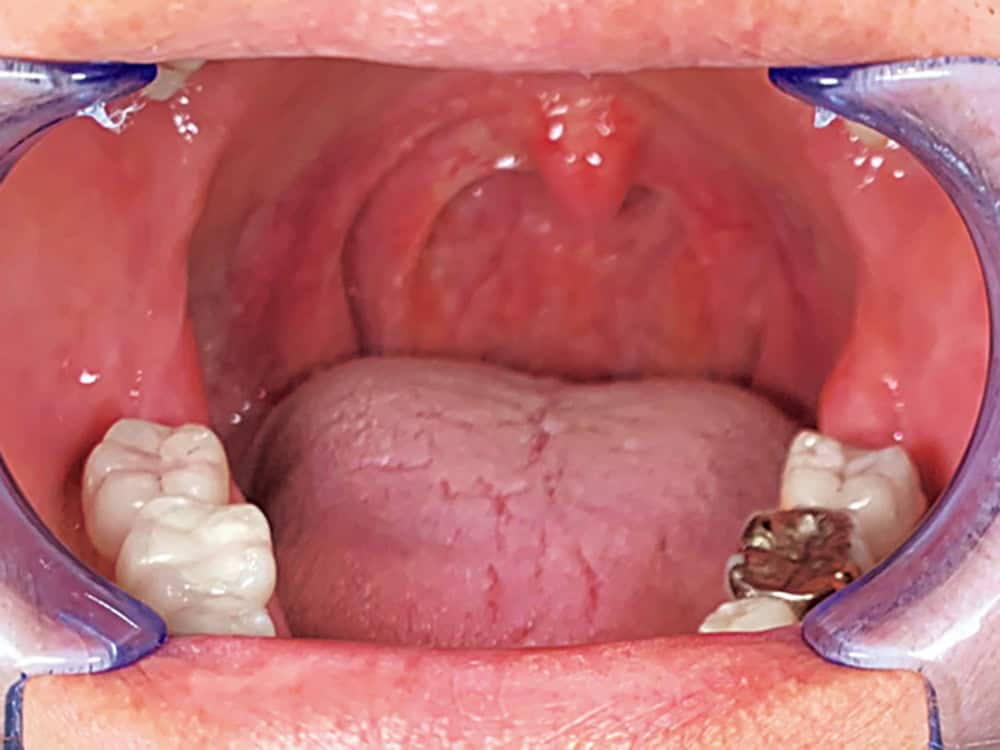

① 舌を吸い上げて上あごにくっつける

口を開けて舌全体を上顎に吸い上げて20秒キープする。舌裏に洞窟を2つ作り、2分間繰り返す。

喉と舌の奥の筋肉をトレーニングすると、口蓋垂(喉ちんこのあたり)を鍛えられる。喉をしっかり上下させ音を鳴らして。

口を閉じたときに、舌が上あごにくっつく定位置にきたらOK!